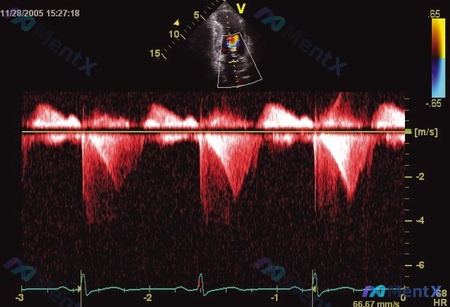

今天整理了一个非常经典的超声读图病例,很容易踩坑,分享一下思考过程。 先看影像资料 这是一张心脏超声的连续波多普勒(CW)图,上方小图是心尖四腔心切面。 第一眼很容易被带偏 初看频谱:基线下方的“双峰”,是不是很像正常的二尖瓣舒张期血流(E峰+A峰)? 如果这时候下“正常”或“轻度二尖瓣病变”的结论...